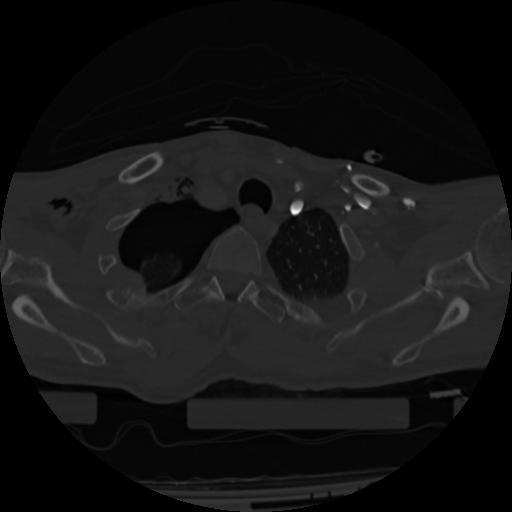

22 ANGIO,CE,Vol,0.5,ANGIO,,